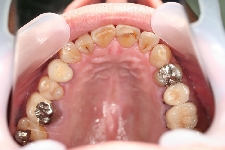

千葉市中央区 H.U様 全顎補綴治療

初診時の口腔内写真

治療終了後の口腔内写真